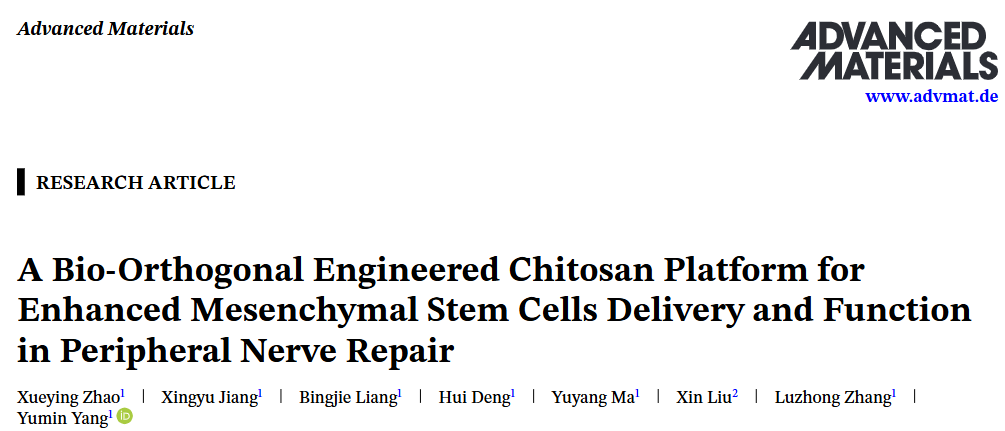

03 (ADV MATER) 用于增强间充质干细胞递送和功能的生物正交工程壳聚糖平台在周围神经修复中的应用

3. (ADV MATER,IF:27.4) 用于增强间充质干细胞递送和功能的生物正交工程壳聚糖平台在外周神经修复中的应用

3. (ADV MATER,IF:27.4) 用于增强间充质干细胞递送和功能的生物正交工程壳聚糖平台在外周神经修复中的应用